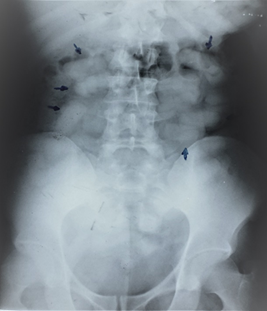

Radiológicamente se puede observar la presencia de objetos o cuerpos extraños radiopacos redondeados u ovalados en el tracto intestinal y se puede ver el "signo de la roseta" o imagen formada por el aire atrapado en el nudo del preservativo y el "signo del doble preservativo, o imagen formada por el aire atrapado entre las capas de látex, que los hacen más visibles. Hay que tener mucha acuciosidad de observar desde el estómago hasta el recto. (7). La tomografía computada, además de observarse las capsulas o cuerpos extraños se puede revelar ocupando el marco colónico casi por completo, con irregularidad en sus contornos, presentado el signo del «jigsaw» o rompecabezas, que ha sido reportado en la literatura y que se origina como producto de láminas de aire intestinal entre el empaquetado y el mesenterio (8)(10).

Se trae a discusión un paciente, de sexo masculino 37 años de edad, nacionalidad extranjera, que ingresa a un hospital público de tercer nivel asintomático, traído por servidores policiales, al ser encontrado en un aeropuerto rumbo a Europa, detectándose por la negativa a ser revisado y nerviosismo a realizar el interrogatorio. Se realizó exámenes de control, radiografía para comprobar la presencia del cuerpo extraño tipo capsulas, ovaladas, luego se realiza una tomografía simple para observar la distancia del recorrido de las capsulas de droga.

Ilustración 1 Radiografía. Presencia de capsulas

Fuente: Hospital de Especialidades Guayaquil “Doctor Abel Gilbert Pontón”.

Autor: Dr. Fernando Moncayo A.